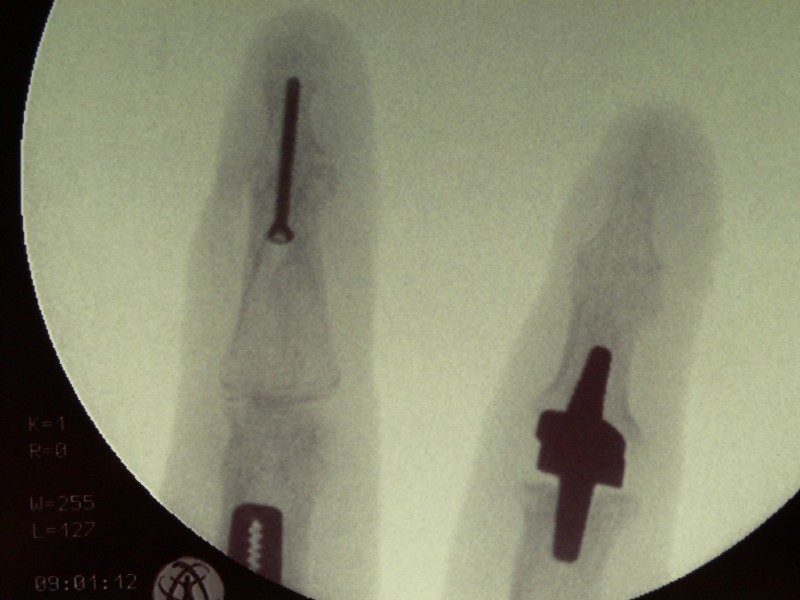

Left: Severe osteoarthritis (abrasion, joint destruction) of the thumb-saddle joint

Middle: Replacement with a hemiarthroplasty pyrocarbon

Right: This patient had, in addition to the thumb-saddle joint osteoarthritis also signs of wear and instability between the wrist bones. She had severe pain and could not use her hand. We reinforced the pyrocarbon endoprosthesis by stiffening three wrist joints. The patient has been symptom-free for over 10 years now and can use her hand without any restrictions.